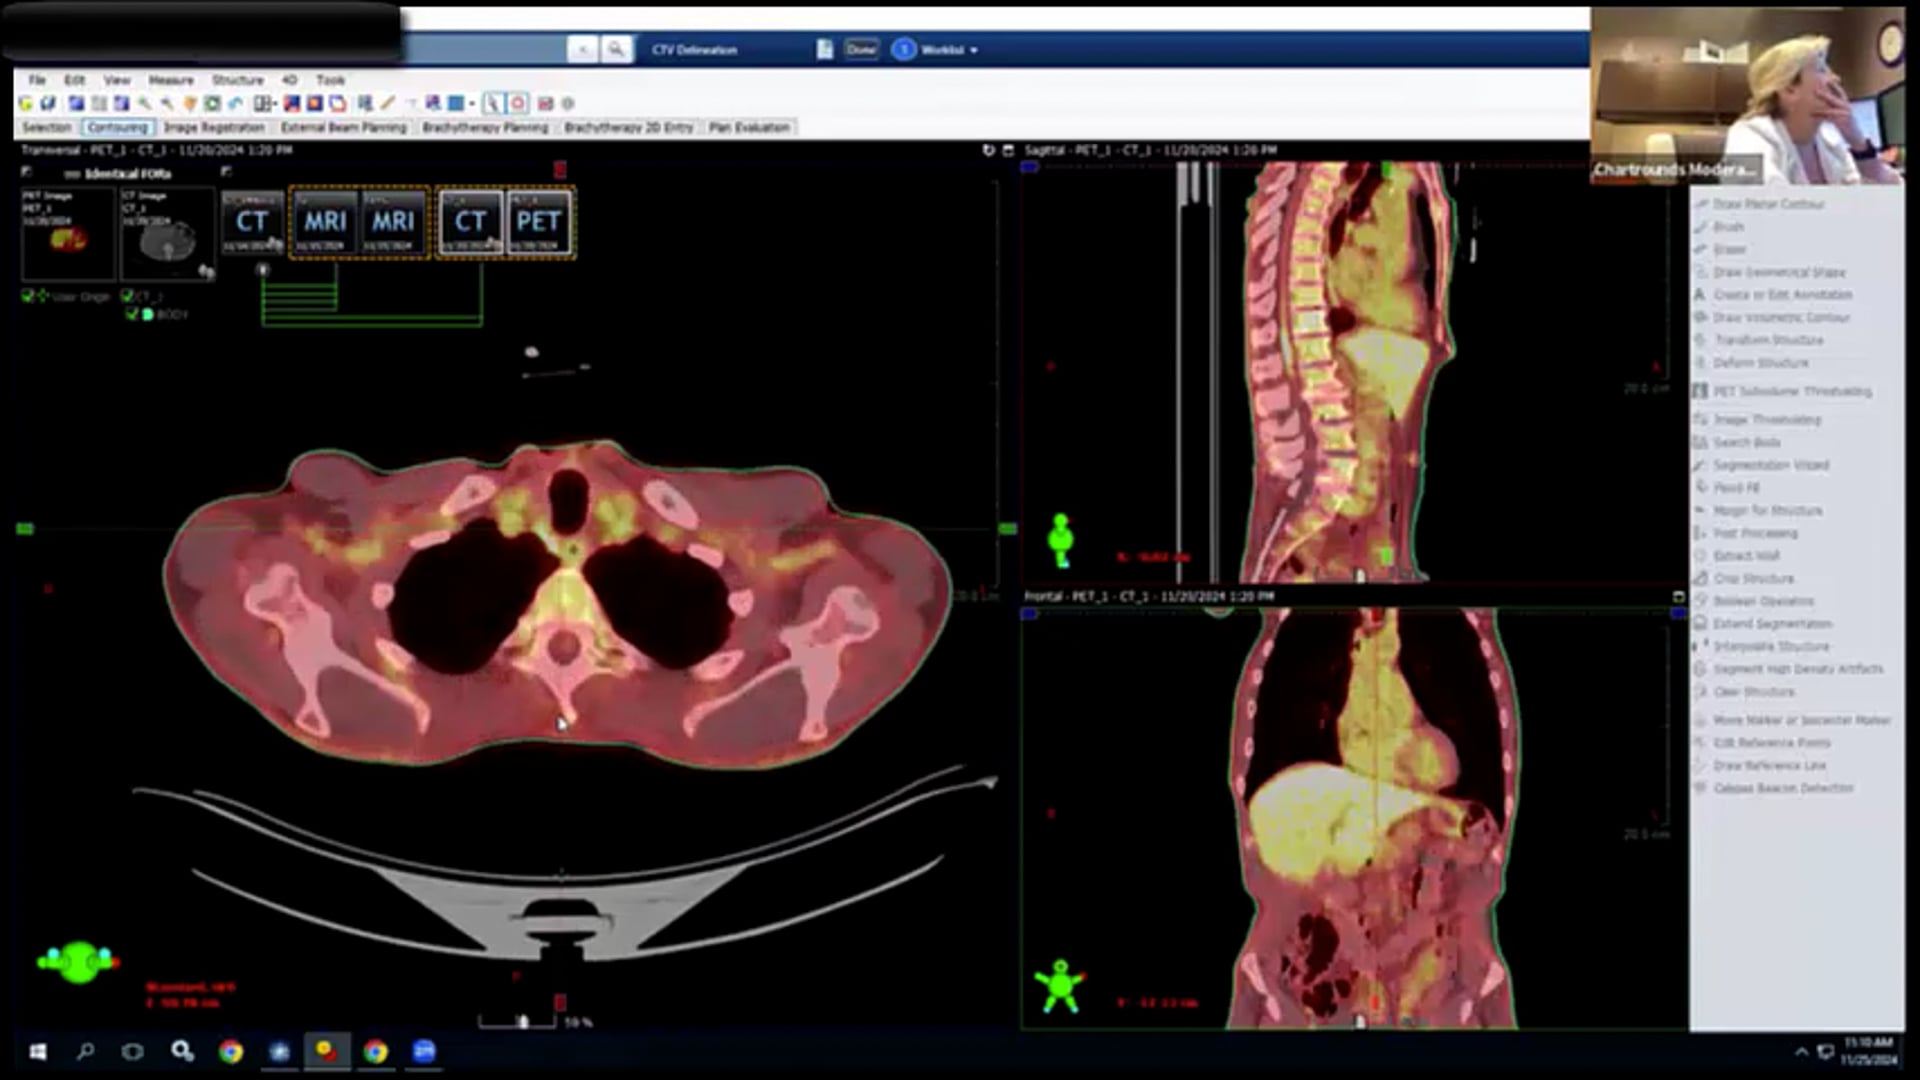

11/25/2024 Dr. Davd Sher - Radiation Oncology - Head and Neck